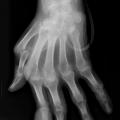

Goutte chronique tophacée

ARTHROPATHIES A CRISTAUX

Image